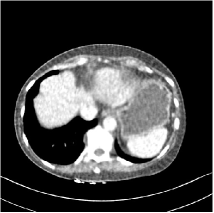

Refer to caption

Fig. 4: FBP images of test examples.